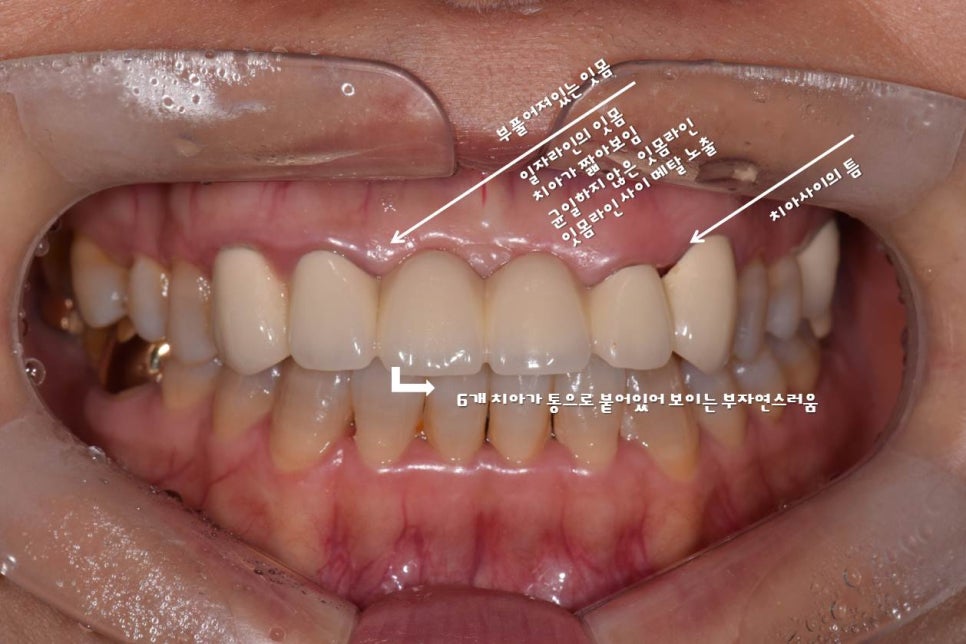

윗니 치아 3번부터 - 3번까지 6개 치아를 브릿지(연결되어 있는 크라운)로 예전에 치료 경험 있는 환자분이 오셨어요. 위 환자분께서는 안쪽엔 금속(메탈)을 포함하고 겉면은 치아색인 PFM 크라운을 사용 중이셨어요.

앞니에 이러한 PFM을 사용 시 치아와 잇몸라인 쪽에 지금처럼 검은 선이 생기게 되죠. 또한 치아 색도 원래의 자가치아보다 색감이 어둡게 나올 수밖에 없습니다. (자가 치아의 색은 약간의 투명감을 띄고 있죠)

환자분은 기존 앞니에 많은 불만을 갖고 계셨어요.

위 사진은 잇.몸.성.형 후 올세라믹 크라운 세팅하셨네요.

치아의 투명도, 크기 ,모양, 잇몸라인 꽤 괜찮아 보입니다. 환자분도 만족하셨고요.

여기서 잠깐. 눈치채셨나요?

잇몸라인의 확실한 변화 아래 사진처럼 잇몸라인의 굴곡은 어느 정도 확실하게 표현되어야 합니다. 통자 몸매가 예쁘지 않듯, 잇몸라인의 굴곡도 있어야 예쁘겠죠?